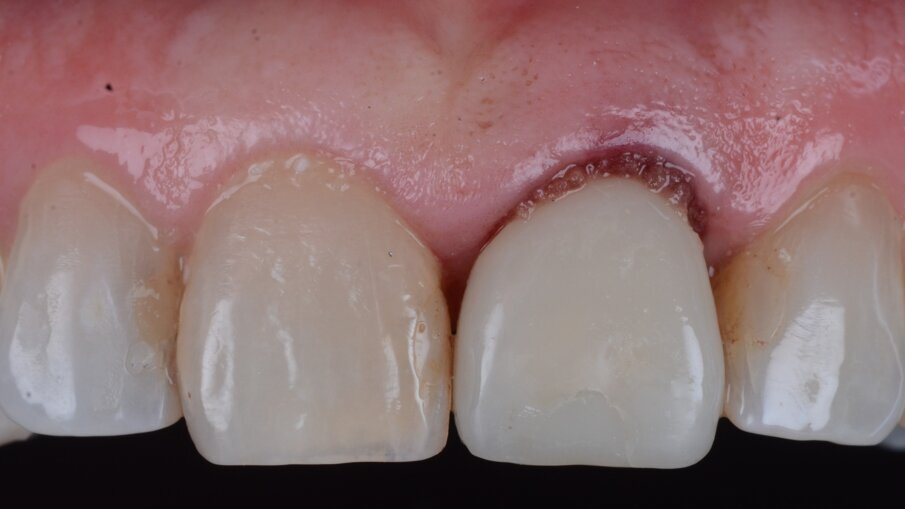

Una paziente di 53 anni si è presentata in studio con un incisivo sinistro fratturato a cui era stata più volte cementata una corona di ceramica (Figg. 1, 2). L’anamnesi e gli esami hanno evidenziato una buona salute sistemica e orale, un’occlusione ben equilibrata e nessuna abitudine al fumo. La tomografia cone beam (CBCT) e la radiografia periapicale hanno mostrato un riassorbimento radicolare esterno con inserimento nell’osso alveolare molto scarso, insufficiente per un adeguato posizionamento di un comune perno endocanalare (Figg. 3, 4). Considerando che il dente fratturato si trovava nella zona estetica, il paziente richiese un restauro nel modo più sicuro e più veloce possibile.

Fig. 1_Situazione iniziale, visione extra-orale.

Fig. 2_Situazione iniziale, visione intra-orale.